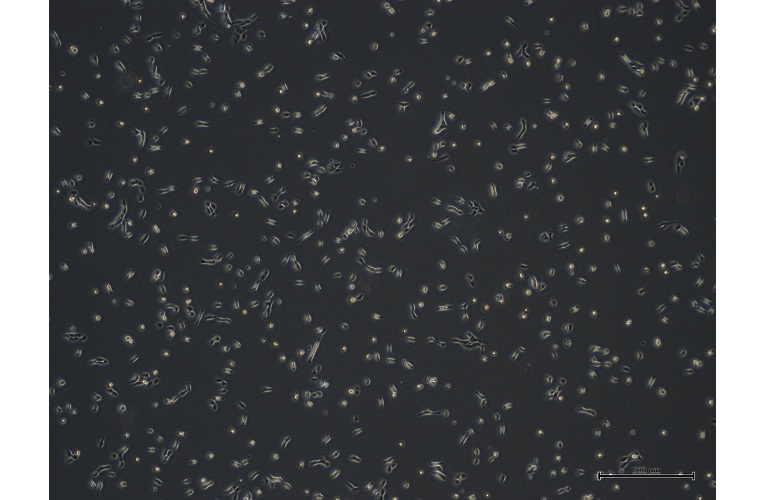

- Morphology: Epithelial

- Growth properties: Adherent

- Characterisation tests: Comprehensive gene expression analysis; Identification of cell proliferation and cellular form; Drug sensitivity tests